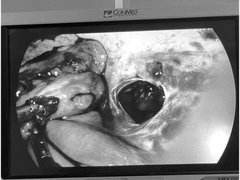

Nhiều bệnh viện bỗng dưng quá tải - vì sao?

Sau một thời gian dịch COVID-19 hạ nhiệt, người dân tuyến dưới bắt đầu đổ lên các bệnh viện tuyến trung ương khám, chữa bệnh khiến nhiều bệnh viện rơi vào quá tải trầm trọng. Có nơi bệnh nhân tăng tới gần 300%, phòng mổ sáng đèn suốt đêm, bác sĩ, nhân viên y tế phải tăng ca, tăng giờ làm lên đến 16 tiếng/ngày, bận rộn với guồng quay công việc từ 6h sáng đến 8-9h tối để phục vụ hết bệnh nhân.